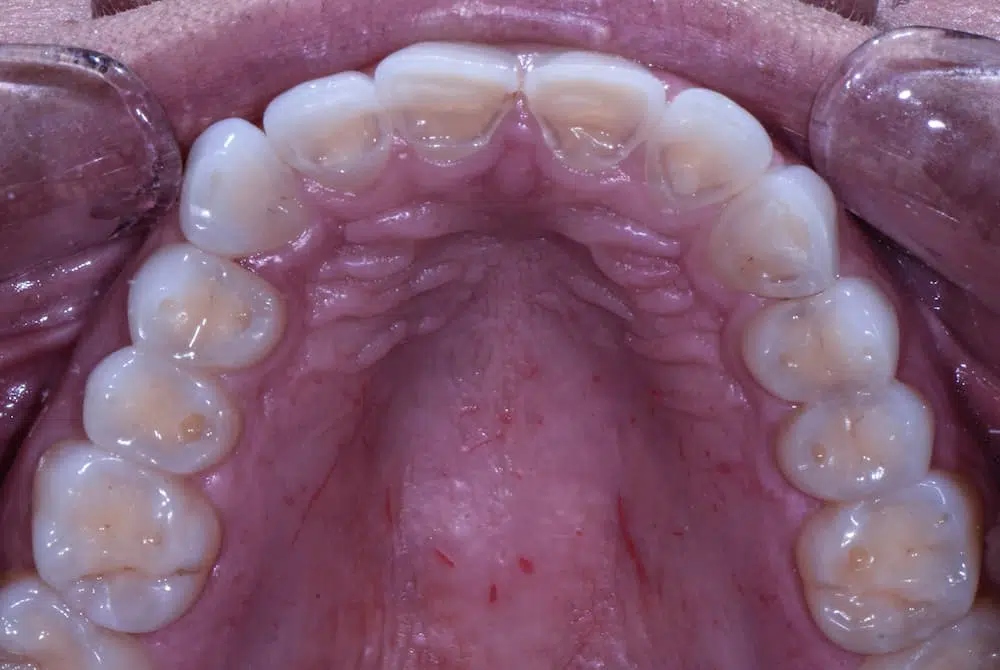

In the photo above, you can see that there is yellow showing through the teeth. This is exposed dentin (the inner layer of the tooth). Dentin wears faster than enamel and can be more sensitive, so it’s important to seek dental treatment if you notice this occurring.